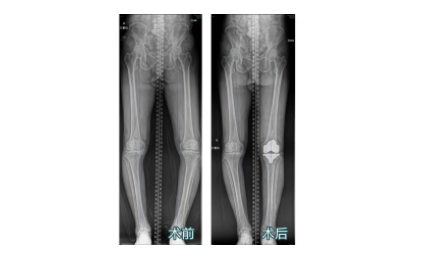

在sararz关节外科,郝亮副主任医师为王大爷进行了系统检查,行X线片显示:左膝内翻、左膝关节骨质增生、膝关节间隙狭窄、髌骨间隙狭窄、关节面硬化,经诊断为“左膝关节骨关节病”。

术前